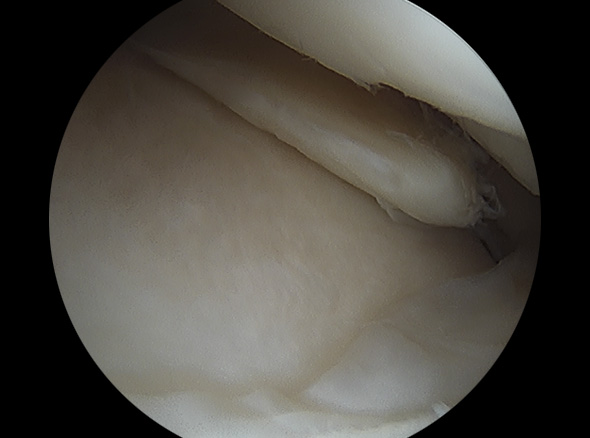

불안정한 반월상연골 부위를 내시경으로 확인하여 파열된 연골판을 꿰맴

반월상 연골판 파열 정도에 따라서 절제술, 봉합술로 나눠 수술을 결정합니다.